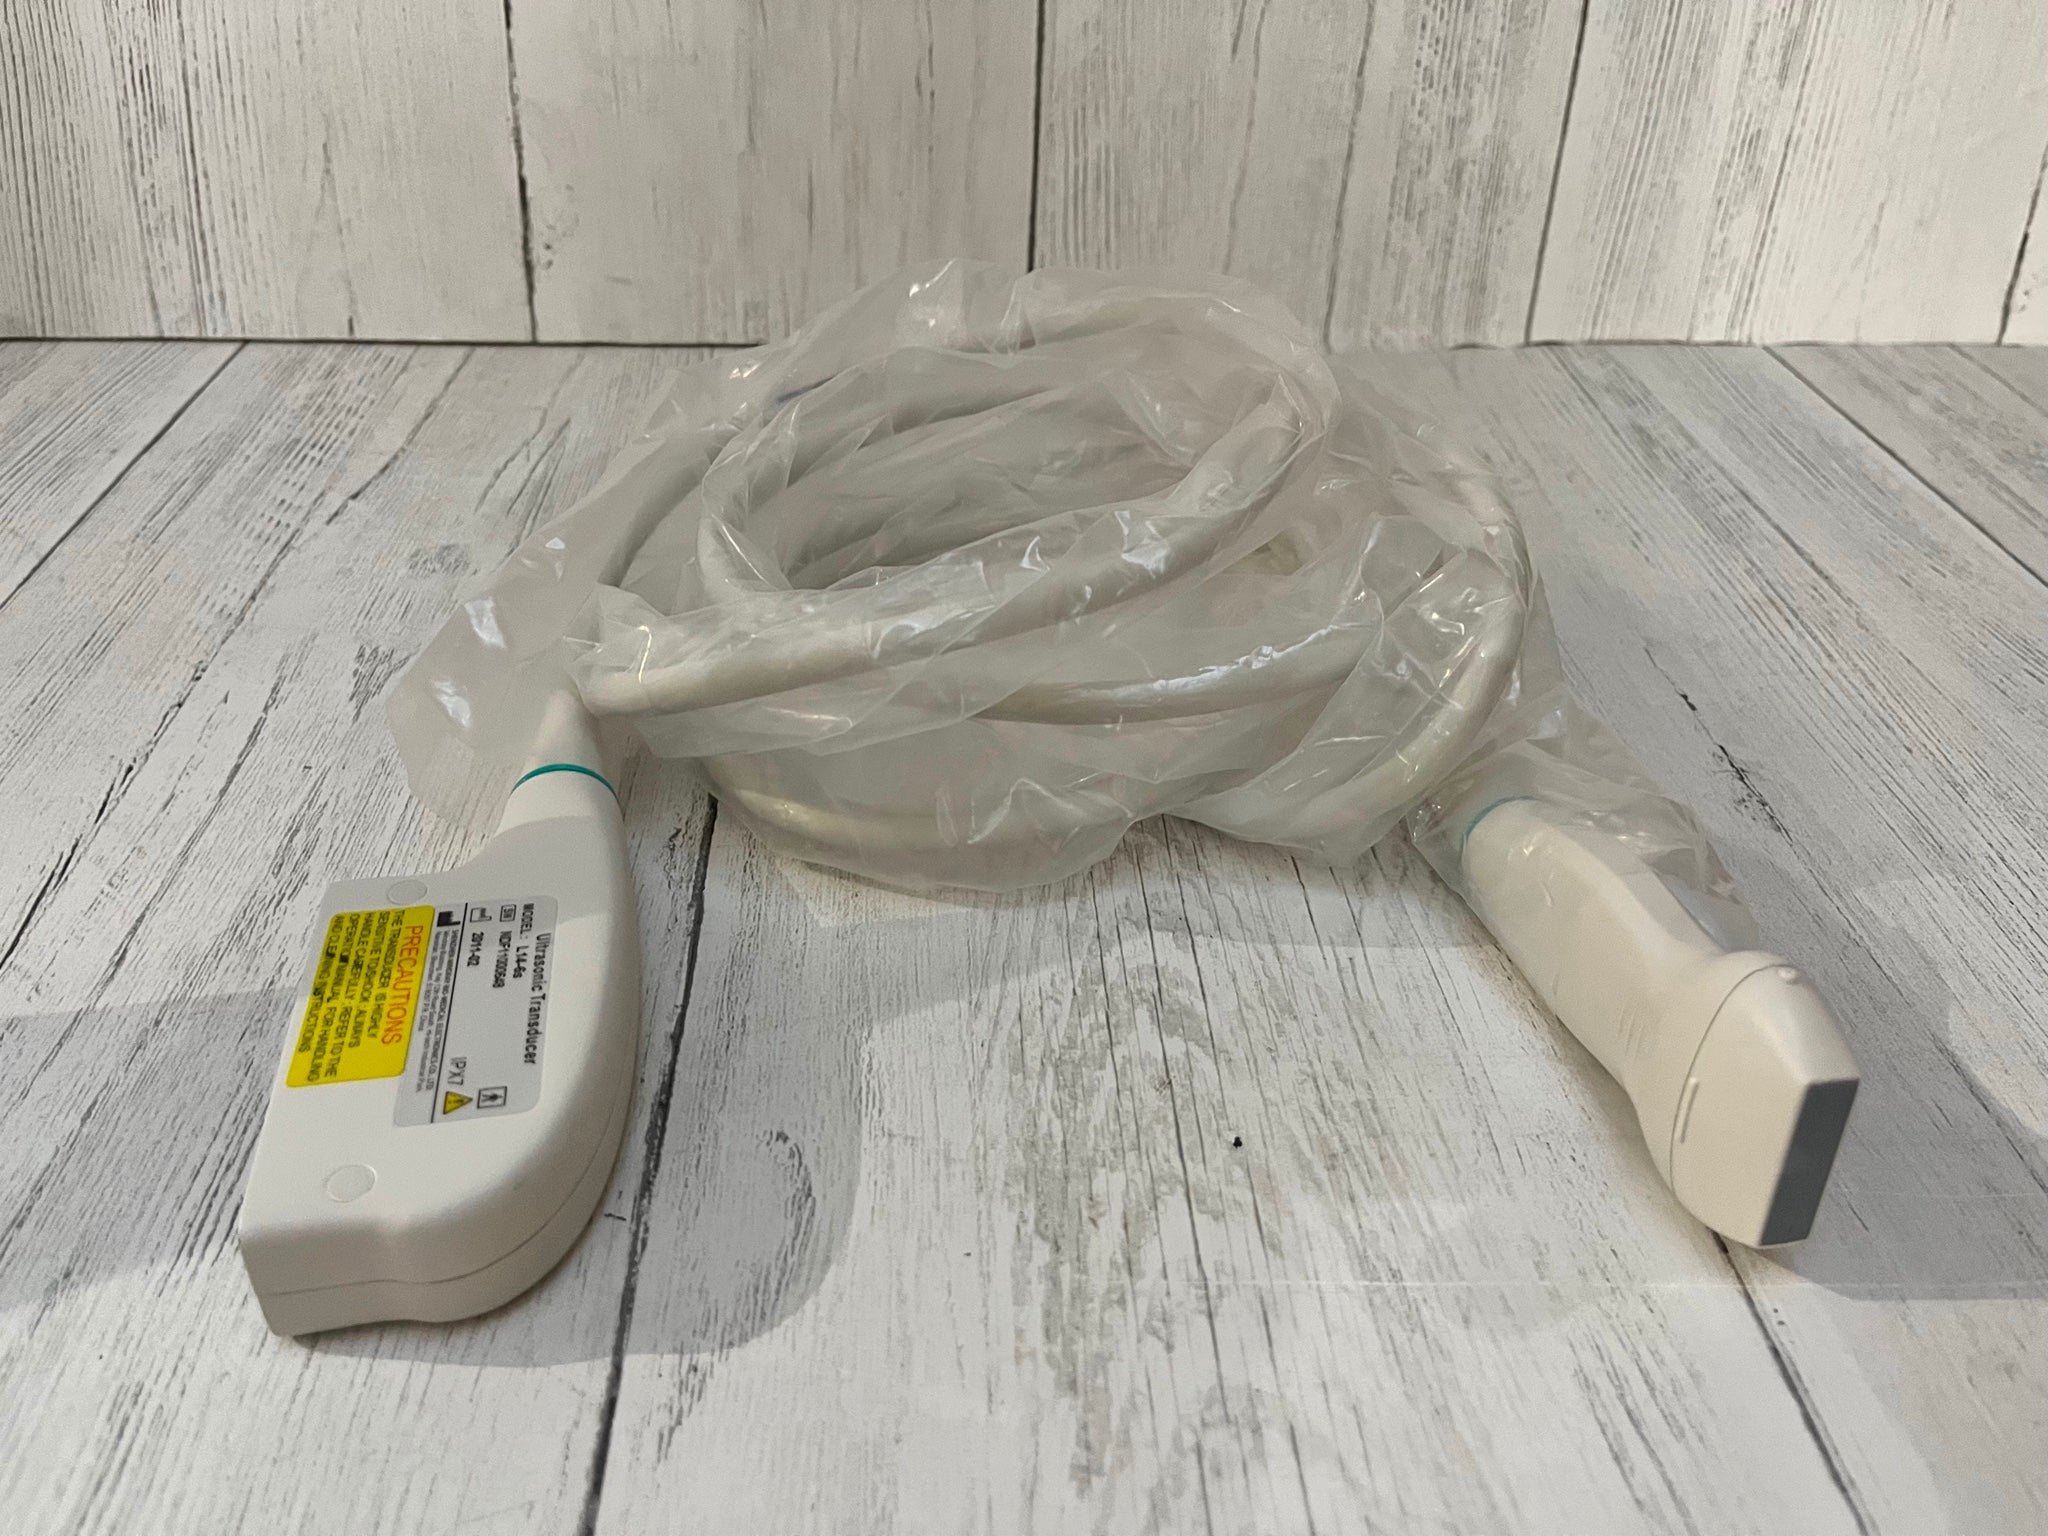

Acquire a trusted healthcare companion with our Philips IU22 3D/4D Ultrasound System, now available for purchase. This pre-owned model, possessing a legacy of reliability, is being offered in an excellent operational condition and comes with a complete set of four probes.

Comprehensive Functionality: Despite showing minimal signs of cosmetic wear, the unit remains fully functional and geared for immediate clinical deployment. All probes have been diligently tested to ensure optimal performance. Extensive care has been taken to maintain the system, reaffirming its condition akin to new.